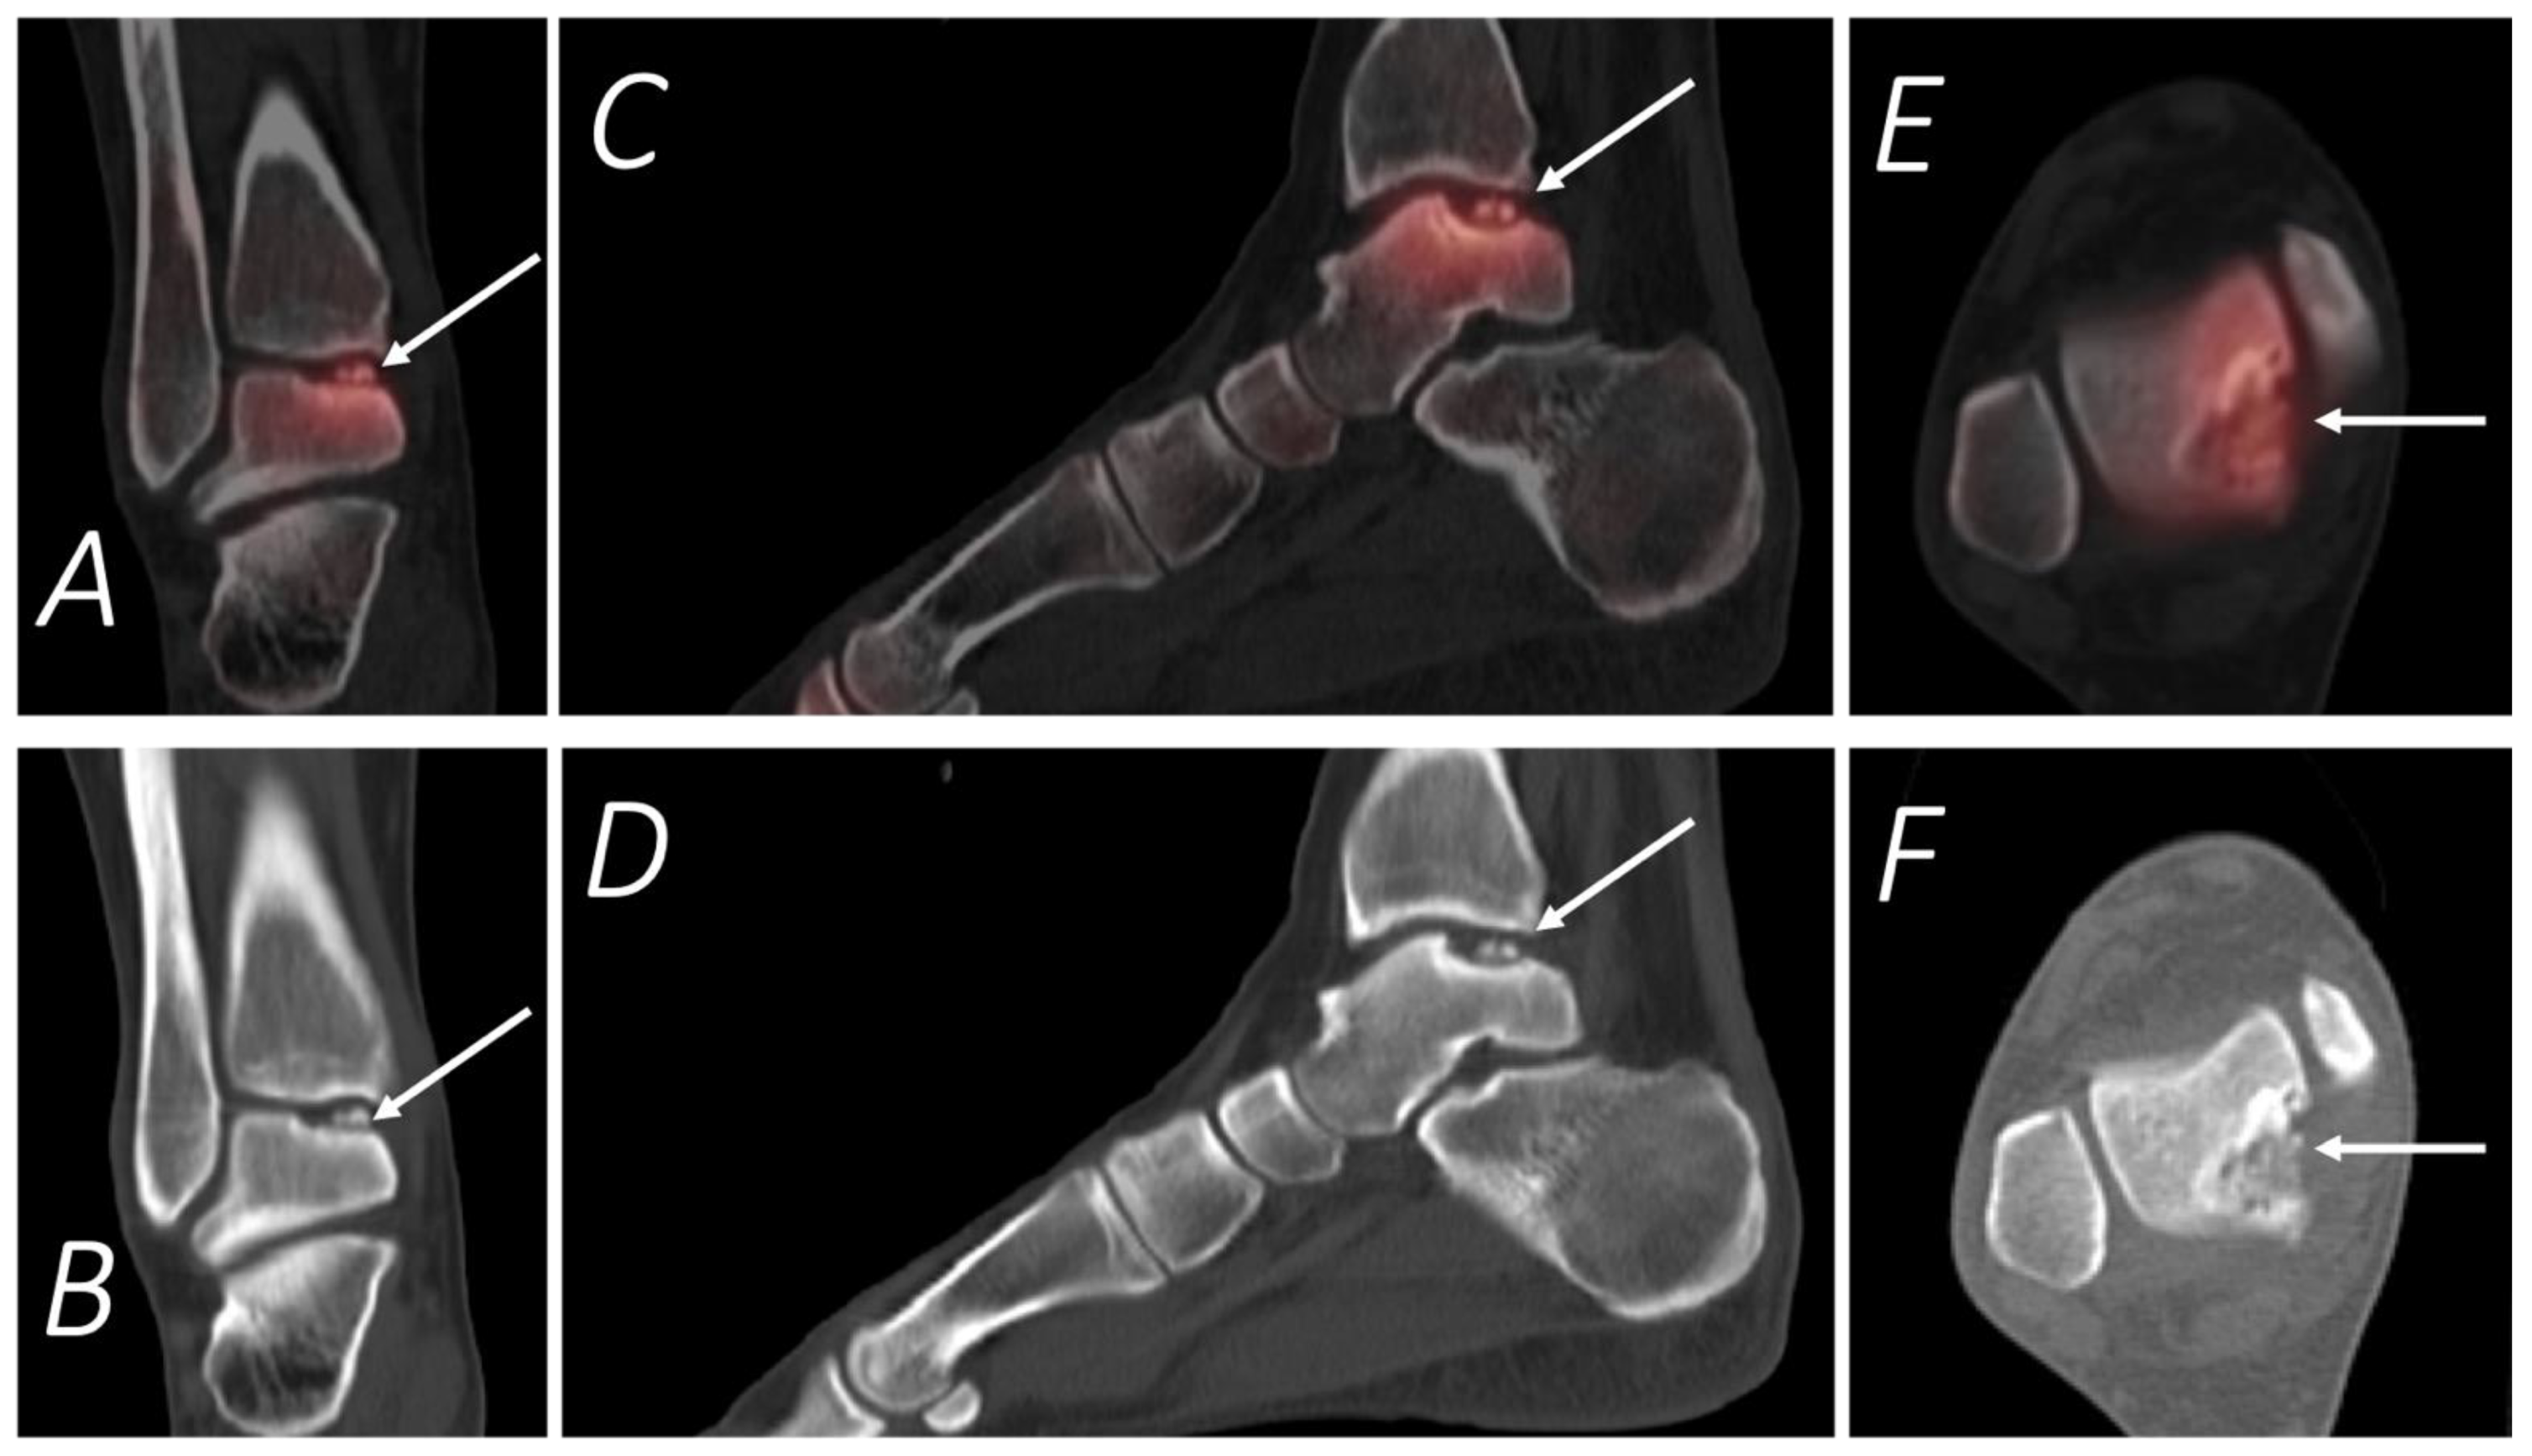

Figure 10.

Thirty-two-year-old female being evaluated for chronic but worsening right ankle pain underwent a Tc-99m MDP bone scan with SPECT/CT. Selected upper panel SPECT/CT and corresponding lower panel CT images of the right ankle in coronal (A,B), sagittal (C,D), and axial (E,F) projections are provided. The white arrow denotes a defect in the posteromedial talar articular cartilage and underlying subchondral bone, which corresponded symptomatically with the region of the patient’s pain.